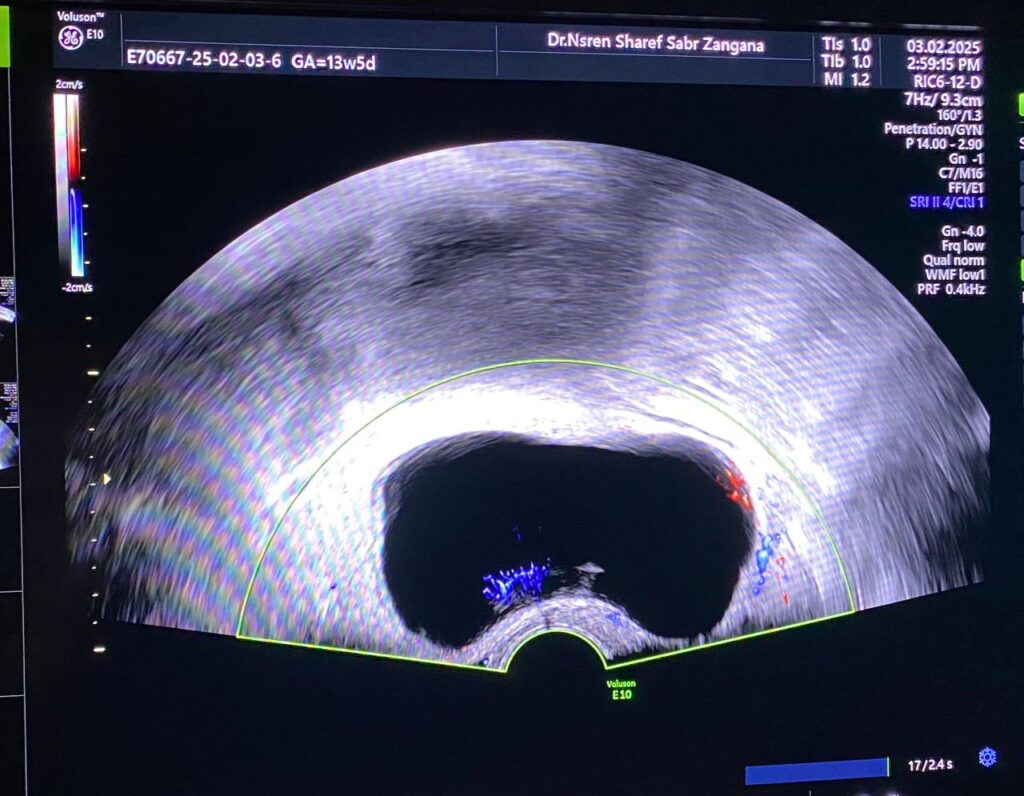

Right Ovarian pedicle Torsion U/S

Right ovarian avascular cystic mass size 75x41mm mostly physiological , with adjacent right adnexal mass size about 33x28mm , picture mostly of twisted ovarian pedicle? but ectopic pregnancy cannot be excluded , please for further study , also associated with small amount of free pelvic fluid <10ml mostly reactionary